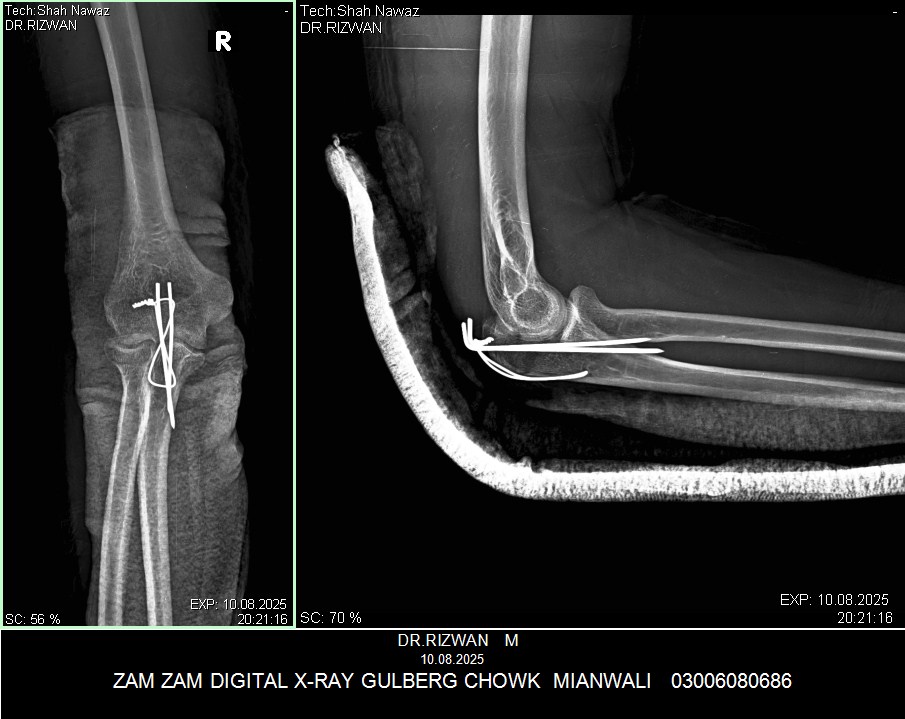

My husband had elbow surgery on 9th of August. I want to know about physiotherapy. When can we start physiotherapy so he can bend and extend his arm freely.Kindly guide us. If we start now will it effect joint or not. TIA

Back slab should be removed and physiotherapy should be started asap with gradual increase in range of motion. otherwise stiffness might occur.

Mostly after 3 Weeks Back slab exchanged with arm and sling and start with protected gentle Range of motion To avoid stiffness

But Final decision will be from operating Surgeon

I would advise you to wait for 6 weeks for elbow Range of motion. keep doing shoulder and wrist ROM from day 1.